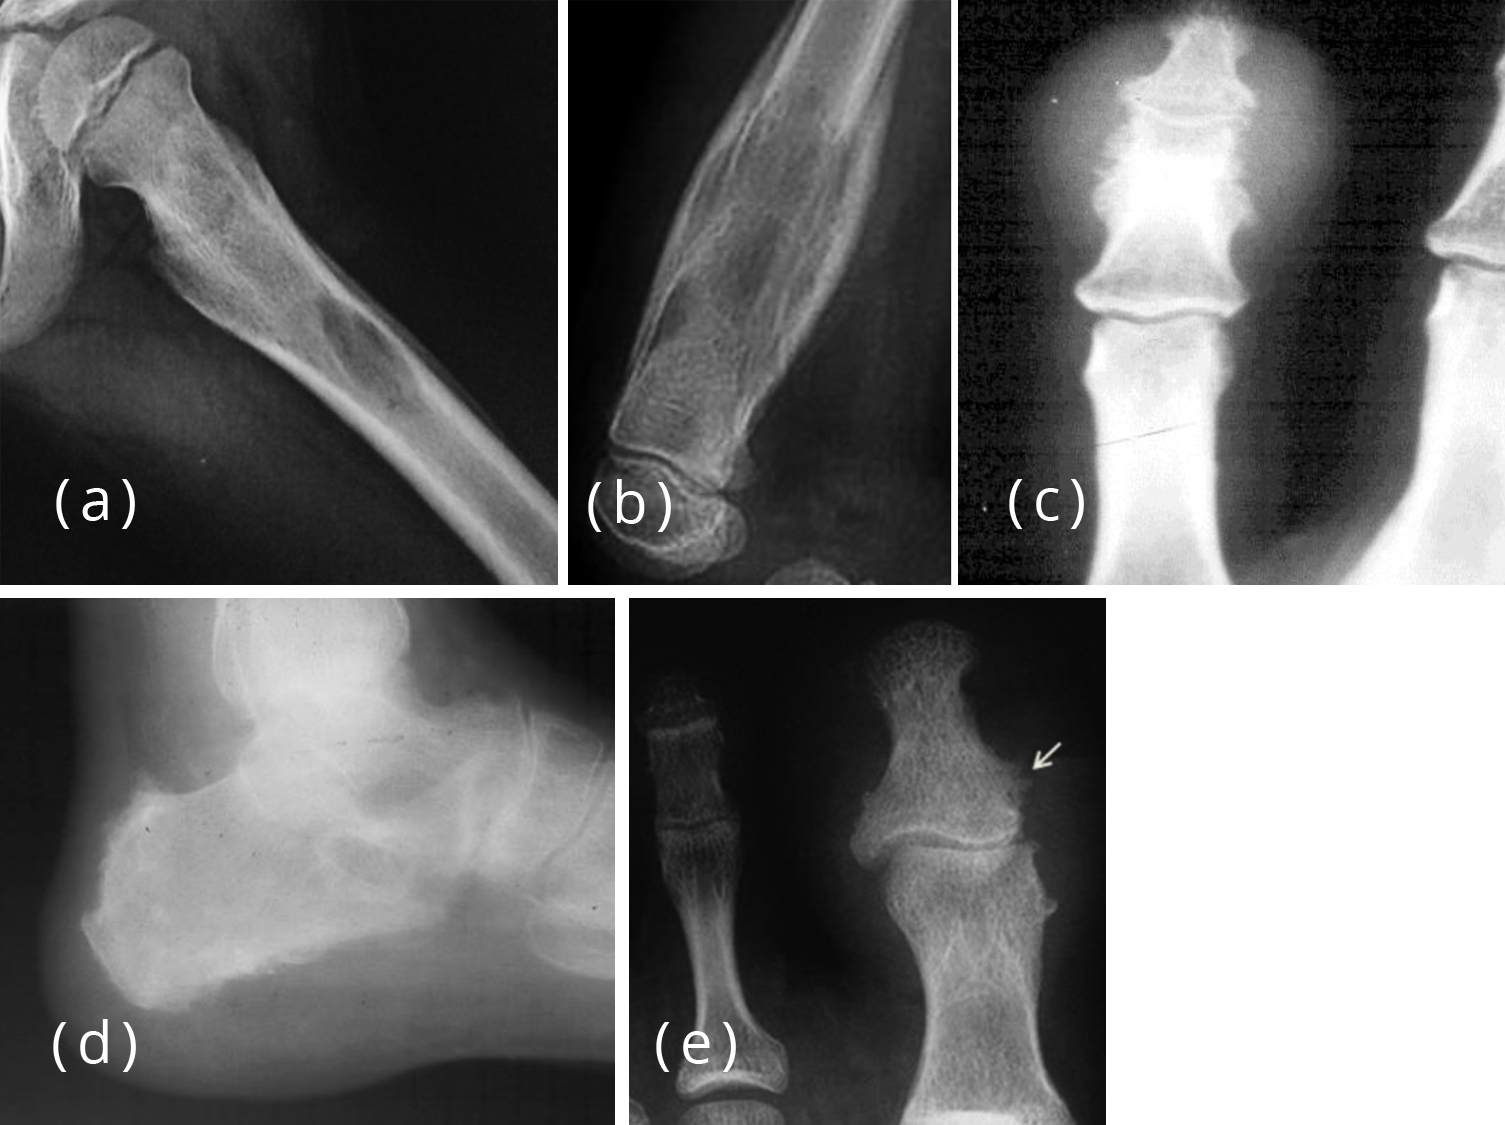

Malignant causes of periosteal reaction in paediatrics part 2 Periosteal Reaction Dental The formation of new bone by periosteum due to an insult is called periosteal bone reaction (pbr). Periosteal reaction results when cortical bone reacts to one of many possible insults. Patterns of periosteal reaction, both in morphology and distribution, are key to distinguishing benign or physiologic periosteal reaction from types of periosteal. Proliferative periostitis is a rare disease, and represents. Periosteal Reaction Dental.

From www.clinicalradiologyonline.net

Imaging of periosteal reactions associated with focal lesions of bone Periosteal Reaction Dental The ultimate goal of any dental treatment is the regeneration of lost tissues. This poster will review the gross and cellular anatomy of the periosteal membrane and a range of periosteal responses. Periosteal reaction results when cortical bone reacts to one of many possible insults. Patterns of periosteal reaction, both in morphology and distribution, are key to distinguishing benign or. Periosteal Reaction Dental.

From www.researchgate.net